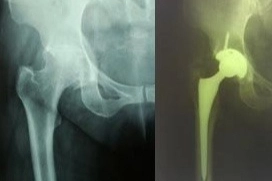

Ο Τερζής Γεώργιος είναι Ορθοπαιδικός Χειρουργός με ιατρεία στη Νέα Σμύρνη και στην Αθήνα (εντός της Κεντρικής Κλινικής Αθηνών). Είναι πτυχιούχος της Ιατρικής Σχολής του Εθνικού και Καποδιστριακού Πανεπιστημίου Αθηνών. Με την ολοκλήρωση των σπουδών του, ειδικεύτηκε στη Γενική Χειρουργική στο Γενικό Αντικαρκινικό - Ογκολογικό Νοσοκομείο Αθηνών "Άγιος Σάββας" και στο 411 Γενικό Στρατιωτικό Νοσοκομείο Τρίπολης. Στη συνέχεια, μετέβη στο Ηνωμένο Βασίλειο, όπου εργάστηκε ως ειδικευόμενος στην Ορθοπαιδική, αποκτώντας πολύτιμη εμπειρία σε όλο το φάσμα των υποειδικοτήτων της ορθοπαιδικής και του τραύματος. Παράλληλα, εκπαιδεύτηκε σε νευροχειρουργικές μονάδες, στη χειρουργική της θωρακικής κοιλότητας και σε Μονάδες Εντατικής Θεραπείας. Κατά τη διάρκεια της επαγγελματικής του πορείας, υπηρέτησε ως Επιμελητής σε κορυφαία Νοσοκομεία του Ηνωμένου Βασιλείου, όπως το Royal United Hospitals Bath, το Mayday University Hospital και το North Middlesex University Hospital. Από το 2001 μέχρι και σήμερα, εργάζεται ως Ορθοπαιδικός Χειρουργός στην Κεντρική Κλινική Αθηνών. Το επιστημονικό του ενδιαφέρον επικεντρώνεται κυρίως στην αρθροπλαστική ισχίου και γόνατος, καθώς και στην αρθροσκοπική αντιμετώπιση παθήσεων του ώμου, του ισχίου, του γόνατος και της ποδοκνημικής. Επιπλέον, εξειδικεύεται στη χειρουργική αντιμετώπιση των καταγμάτων του ισχίου. Ιδιαίτερη έμφαση δίνει στην εφαρμογή σύγχρονων χειρουργικών τεχνικών που μειώνουν τον χρόνο της επέμβασης, αξιοποιώντας ελάχιστα επεμβατικές μεθόδους, με στόχο τη βελτιστοποίηση της μετεγχειρητικής ανάρρωσης, τη μείωση του μετεγχειρητικού πόνου και τον ελαχιστοποίηση του χρόνου νοσηλείας.